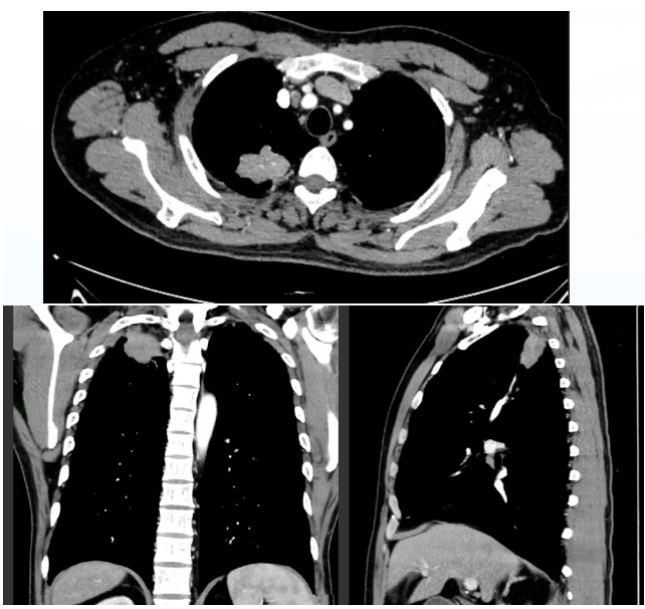

继续服药3个月,2024年3月11日再次复查胸部CT:病灶吸收良好,纵隔窗基本看不到病变(图8)

8  患者胸部CT(2024年3月11日)

后续该患者服用复方新诺明0.96 g bid 8周。目前患者无症状,计划2025年3月复查胸部CT。